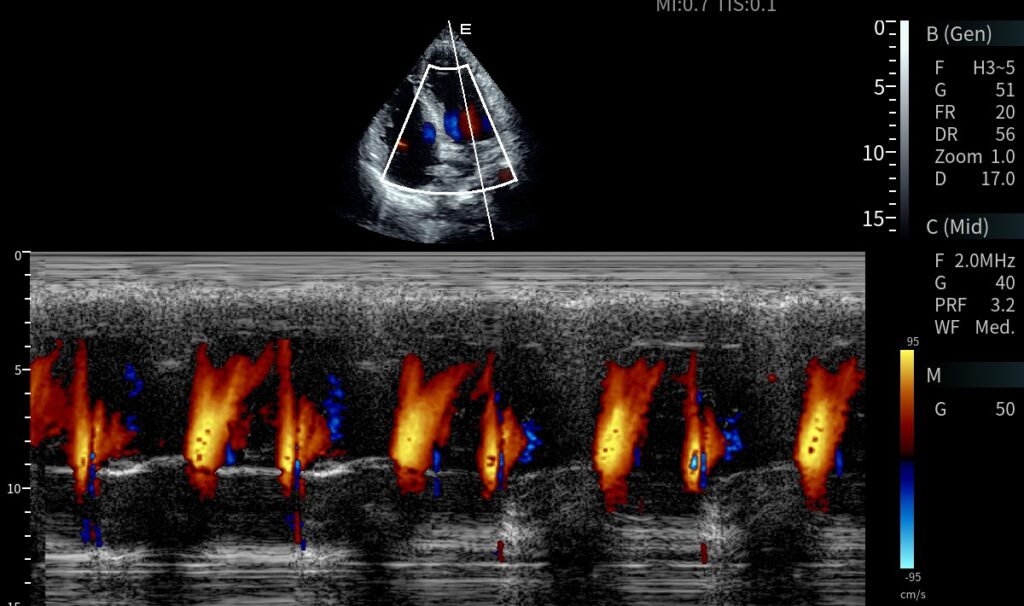

O modelo conta com arquitetura digital avançada, suporte para múltiplos transdutores, Doppler colorido de alta definição e interface otimizada que facilita o fluxo de trabalho. Sua estrutura estacionária proporciona estabilidade, conforto ergonômico e alta produtividade em rotinas intensivas de diagnóstico, como exames cardíacos, obstétricos e vasculares.